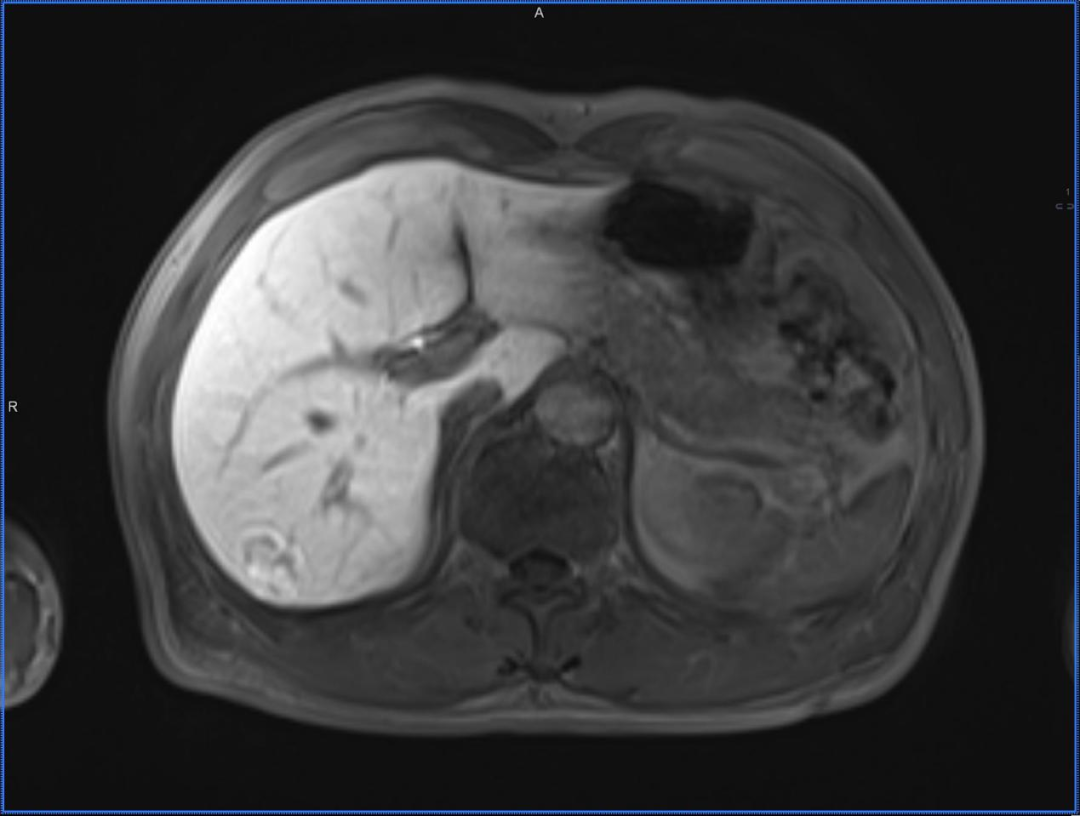

Royal Lee Cancer Center MRI with Primovist® contrast enhancement imaging data

Patient History: Female, 28 years old, with a history of hepatitis B for over ten years; AFP: 55.3.

Ultrasound from the previous hospital showed a space-occupying lesion in the right anterior lobe, and CT enhancement suggested primary liver cancer in segment S7.

Recently, MRI with Primovist® contrast enhancement revealed a lesion in segment S7 of the liver, with low signal on T1WI, slightly high signal on T2WI, high signal on DWI, and dynamic enhancement showing rapid wash-in and wash-out, with the lesion showing hypointensity in the hepatobiliary phase.

After the MRI with Primovist® contrast enhancement, it was found that there was a mass in segment S7 of the right liver lobe. After comprehensive discussion, the radiologist considered it to be focal nodular hyperplasia (FNH) of the liver.